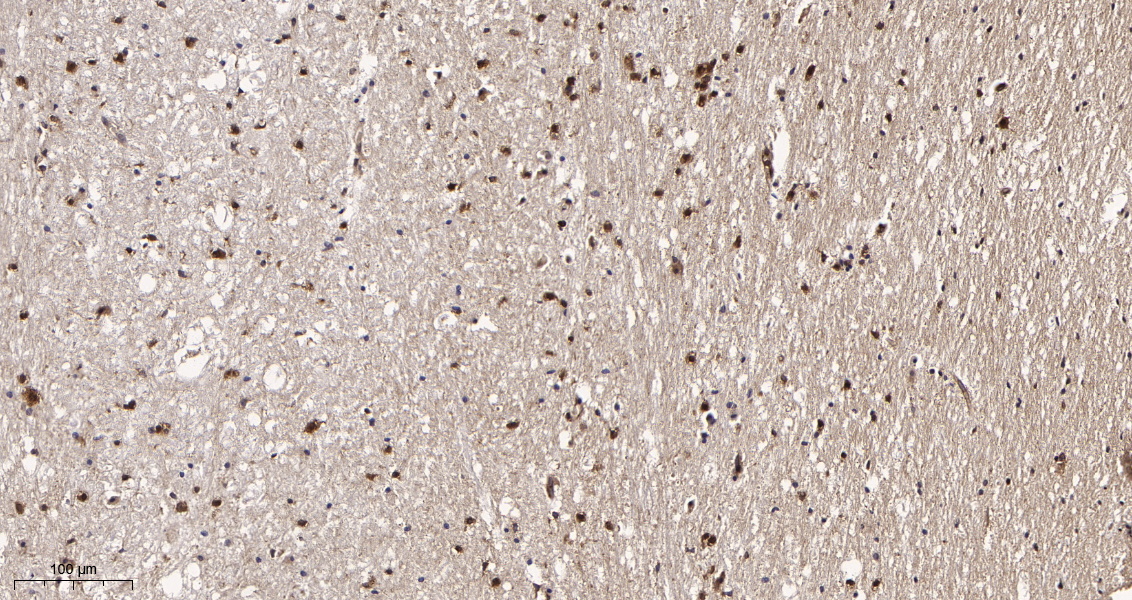

产品名称DRP1 (5F8) Rabbit Monoclonal Antibody

推荐应用WB,IHC-P,IF-P,IF-F,IF-ICC,IP,ELISA

稀释度IHC-P 1:200-1000,WB 1:1000-5000,IF-P/IF-F/IF-ICC 1:200-1000,ELISA 1:5000-20000,IP 1:50-200

背景介绍This gene encodes a member of the dynamin superfamily of GTPases. The encoded protein mediates mitochondrial and peroxisomal division, and is involved in developmentally regulated apoptosis and programmed necrosis. Dysfunction of this gene is implicated in several neurological disorders, including Alzheimer's disease. Mutations in this gene are associated with the autosomal dominant disorder, encephalopathy, lethal, due to defective mitochondrial and peroxisomal fission (EMPF). Alternative splicing results in multiple transcript variants encoding different isoforms. [provided by RefSeq, Jun 2013].

功能catalytic activity:GTP + H(2)O = GDP + phosphate.,function:Functions in mitochondrial and peroxisomal division probably by regulating membrane fission. Enzyme hydrolyzing GTP that oligomerizes to form ring-like structures and is able to remodel membranes. May also play a role on organelles of the secretory pathway.,miscellaneous:Isoform 1 and isoform 2 inhibits peroxisomal division when overexpressed while isoform 3 and isoform 4 have no effect.,PTM:Phosphorylated by GSK3B.,similarity:Belongs to the dynamin family.,similarity:Contains 1 GED domain.,subcellular location:Mainly cytosolic. Also membrane-associated. Localizes to mitochondria at spots of division events. Associated with peroxisomal membranes, it is recruited in part by PEX11B. May also be associated with endoplasmic reticulum tubules and cytoplasmic vesicles and found to be perinuclear.,subunit:Homotetramer; N-terminal part binds to the C-terminal part of another DNM1L. Can self-assemble in multimeric ring-like structures. Interacts with FIS1 (By similarity). Interacts with GSK3B.,tissue specificity:Ubiquitously expressed with highest levels found in skeletal muscles, heart, kidney and brain. Isoform 1 is brain-specific while isoform 3 and isoform 4 are predominantly expressed in testis and skeletal muscles respectively. Isoform 2 is weakly expressed in brain, heart and kidney and isoform 5 is dominantly expressed in liver, heart and kidney.